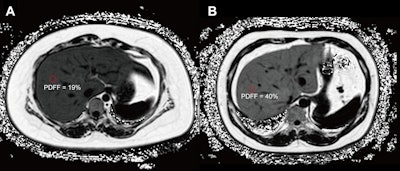

Axial proton density fat fraction (PDFF) maps show hepatic steatosis assessment in patients with dysglycemia. (A) PDFF map in a 27-year-old female patient (body mass index [BMI; calculated as weight in kilograms divided by height in meters squared] = 38.9) with a 1-year history of obesity and metabolic syndrome, and hospital-confirmed prediabetes. The image shows moderate hepatic steatosis (mean liver PDFF, 19%; circle). (B) PDFF map in a 40-year-old male patient (BMI = 33.35) with a history of obesity, metabolic syndrome, hypertension, and hospital-confirmed type II diabetes. The image shows severe hepatic steatosis (mean liver PDFF, 40%; circle). RSNA

“These findings underscore the clinical significance of quantifying liver PDFF, even at mild stages, in this high-risk population,” the researchers wrote.

By quantifying PDFF values, even at low levels of steatosis, radiologists can gain clinically actionable information that will help guide patient management and prevention, the researchers suggested.